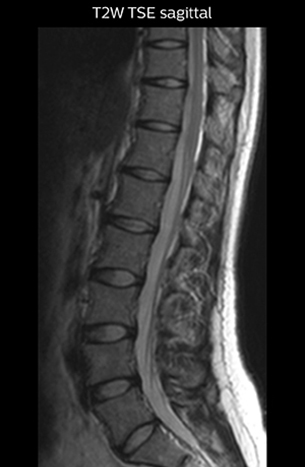

“For example, in sagittal images, when the presence of fat is observed in the intervertebral foramen, it suggests that there is a margin around the nerve. Similarly, the absence of fat indicates that the nerve is being compressed. So, we used to deduce nerve compression indirectly. With NerveVIEW, however, we can observe the condition of the nerves directly, regardless of the presence or absence of fat. We always prefer such direct observation of anatomy over having to make an inference about it.”

“Although symptoms of typical disc herniation and atypical hernia are very similar, the actual site of herniation is different. It is therefore important to characterize the nerve’s condition both inside and outside of the intervertebral foramina. “Conversely, if we see no abnormality in NerveVIEW, we can assume at least that there is no severe condition that requires surgery. Like this, it can help us avoid unnecessary surgery. NerveVIEW can have a tremendous impact in this way.”

“NerveVIEW is really useful for those cases where a nerve disorder is strongly suspected based on the clinical examination but our regular MRI images do not show any findings. These atypical herniations and spinal canal stenosis, occurring in 5% to 15% of the total lumbar herniation/stenosis cases are our main target when using NerveVIEW,” says Dr. Yabuki.